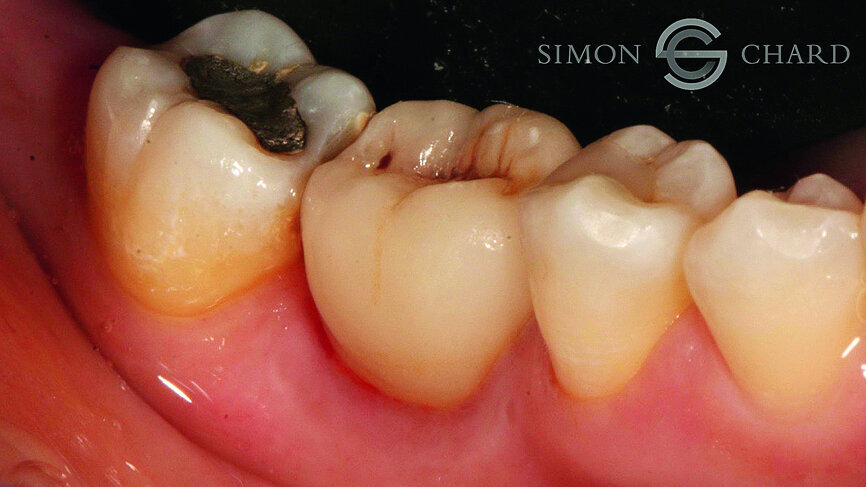

This case report highlights a novel method of restoring implants utilising the modern advances in digital intraoral scanning and chairside milling. It illustrates how an aesthetic single implant retained crown can be provided chairside without the need for analogue impressions (Figs. 1 & 2: Pre-operative condition).

Following a discussion of the options for replacement of LR6, the patient elected for an implant-retained solution. A MegaGen AnyRidge 4 x 10 mm implant was placed utilising a surgical guide for position of the pilot hole. An immediate temporary crown was fabricated using the MegaGen fuse abutment and DMG Luxatemp. A silicone index of the diagnostic wax-up was fabricated and the temporary crown was polished and taken out of occlusion while the implant fully integrated (Fig. 3).